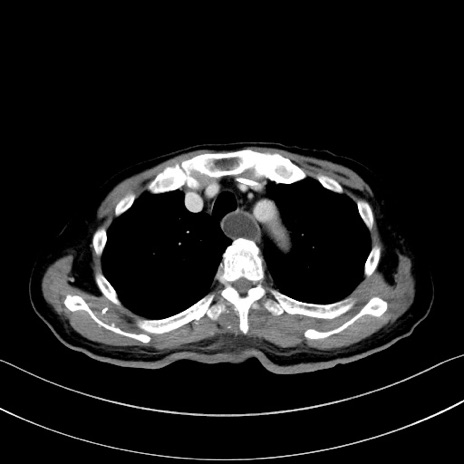

冠状断像

【症例】60歳代男性

【主訴】嘔吐

【現病歴】胃癌にて胃全摘後。食思不振が悪化し、夜中に嘔吐することがある。

【既往歴】胃癌、胃全摘、脾摘、胆摘後

【データ】WBC 5900、CRP 10.56